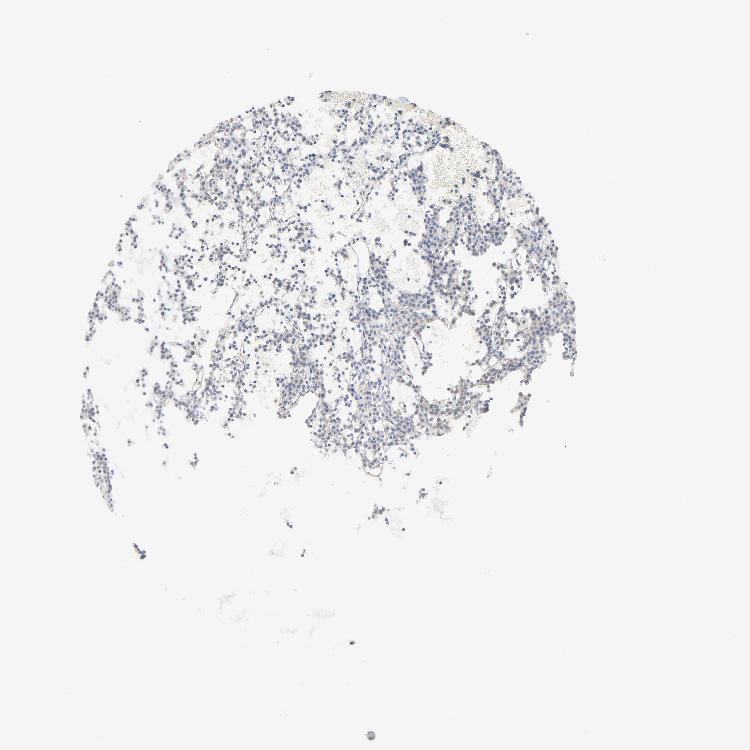

PARATHYROID GLAND - Antibody stainingi

Antibody staining in the annotated cell types in the current human tissue is reported as not detected, low, medium, or high, based on conventional immunohistochemistry profiling in selected tissues. This score is based on the combination of the staining intensity and fraction of stained cells.

Each image is clickable and will lead to virtual microscopy that enables deeper exploration of all samples and also displays staining intensity scores, fraction scores and subcellular localization as well as patient and tissue information for each sample.

Antibody HPA003438

Glandular cells Not detected